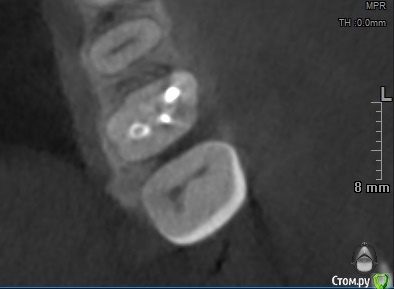

Sier10 Опубликовано 11 марта, 2021 Поделиться Опубликовано 11 марта, 2021 Здравствуйте, не стал открывать новую тему, пожалуюсь тут Прекрасная девушка, 38 лет, 26 зуб, ничего не беспокоит, на клкт периодонтит. Лечили лет 13 назад, кажется, по поводу пульпита. По плану ретрит, дальше протезирование. Удалил свш, дезобтурировал каналья, пытаюсь залезть в мб2 - тщетно. Кажется, нашел устье, 06 файл цепляет но не лезет. Смущает небное смещение устья, если это оно... Кальций. Через две недели повторное посещение.Судя по снимку мб корень имеет плоский профиль и нерегулярный мб канал. Ваше мнение, стоит ли дальше вести поиск мб2 мезиальнее? Ссылка на комментарий

St. Опубликовано 12 марта, 2021 Поделиться Опубликовано 12 марта, 2021 Да, скорее всего он медиальнее от того что искали. Возьмите твердосплав на микромотор и аккуратно уберите навес дентина от медиально щечного по медиальной стенке Ссылка на комментарий

Бардо Опубликовано 8 апреля, 2021 Поделиться Опубликовано 8 апреля, 2021 Я б навес мезиальный чуть убрал еще лонгнеком. Вы скорее всего под навес лезете файлом и он упирается в стенку 1 Ссылка на комментарий